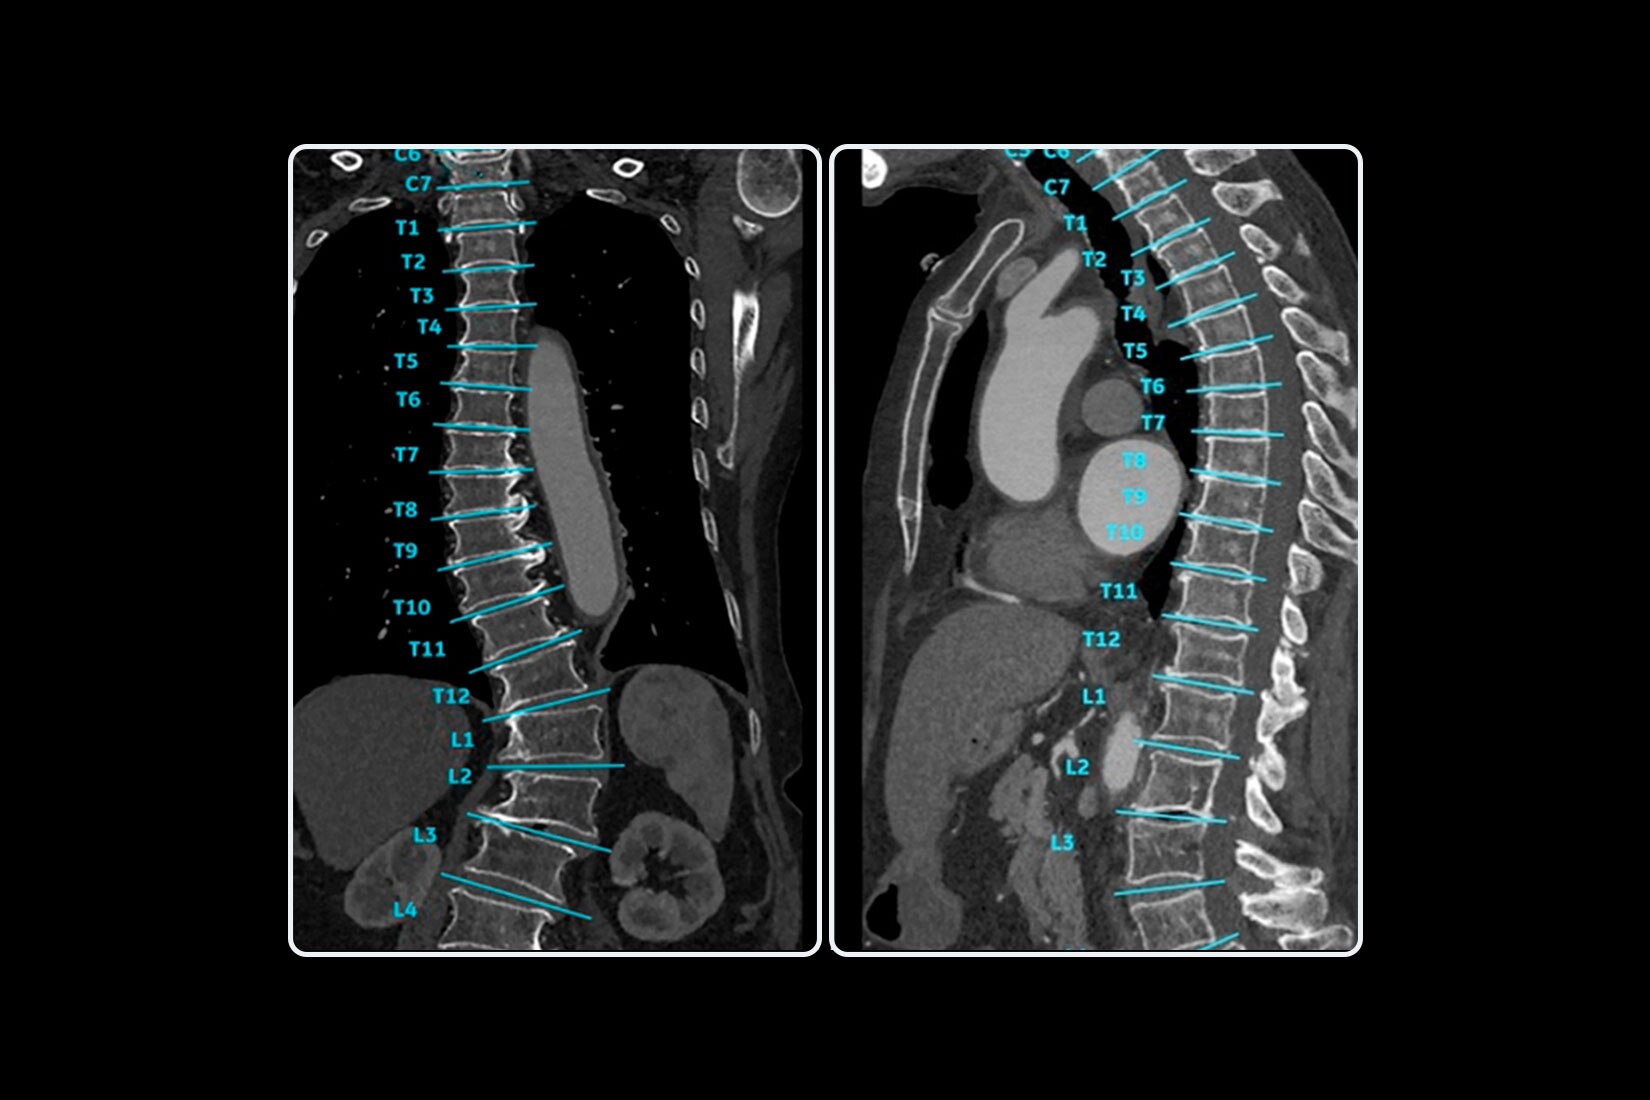

• Sincronizzazione automatica delle fasi da TCA multifase (mCTA)

• I layout intelligenti si regolano automaticamente per visualizzare fino a 6 fasi mCTA contemporaneamente

• Le immagini CTA sono visualizzate automaticamente in una MIP 2D spessa con impostazioni WW/WL ottimizzate